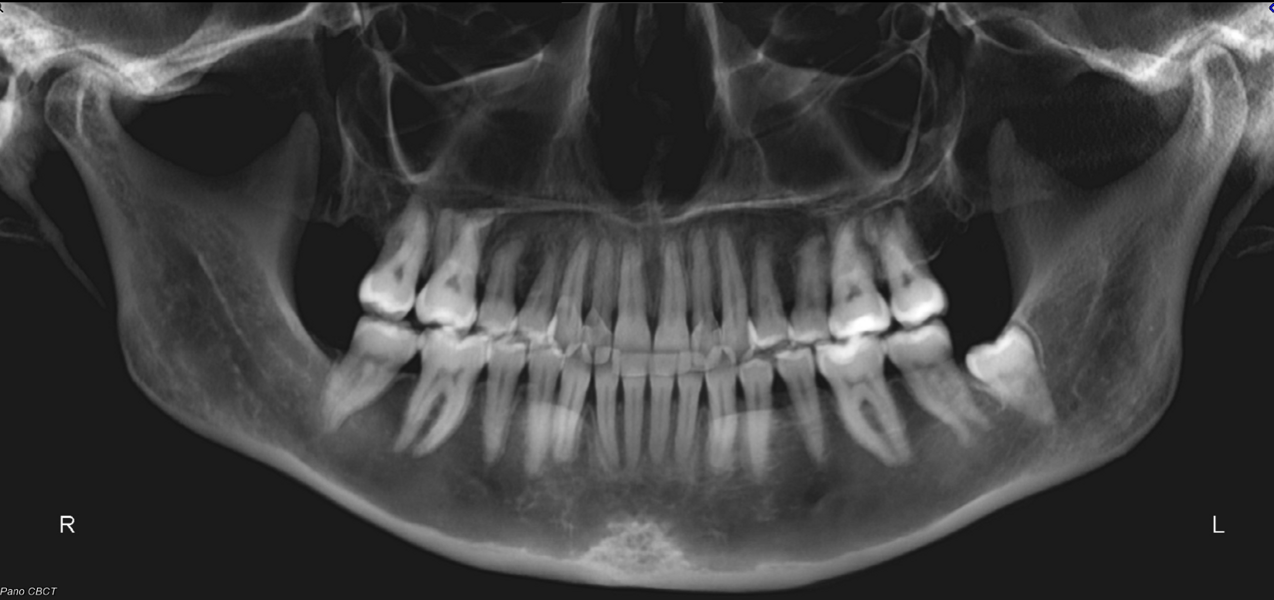

A 30-year-old female patient presented with the chief complaints of severe muscle and joint pain, open bite and tooth wear. She was treated orthodontically as a teenager with fixed appliances. Extra-orally, we observed slight mandibular asymmetry with deviation of the chin to the right, as well as lip incompetence, insufficient chin projection and a long face typical of a dolichofacial skeletal pattern (Fig. 2). Intra-orally, she had an anterior open bite, retroclined maxillary incisors, moderate crowding in both arches, an asymmetrical arch form uneven gingival margins, a mandibular midline shifted to the right, abfractions, gingival recession and wear facets (Fig. 3). The joint and muscle examination revealed pain on palpation of the masseter, temporalis, and superior right and left lateral pterygoid muscles. She also exhibited pain in the bilaminar zone and both lateral poles of the condyles. Clinically, she had early clicking during mandibular opening and closing owing to anterior displacement of the articular disc in both joints. In the dental panoramic tomogram, she was missing all four third molars, but had no other noteworthy pathology (Fig. 4). Cephalometrically, she had a dolichofacial skeletal pattern and proclination of the mandibular incisors (Fig. 5).

We performed a visual treatment objective, and our goals were to lingualise the mandibular incisors, decrease the vertical dimension through intrusion of the posterior teeth and produce anticlockwise rotation of the mandibular plane. This would improve the patient’s facial profile, lip competence and articular function. The CBCT images of the joints showed that both condyles were improperly located within the fossae (Fig. 6). The joint spaces were increased and the condyles descended. The airway area on the CBCT scan showed compression (Fig. 7). The patient was referred for a polysomnographic study to rule out compromised respiratory function.

When measuring the size of her teeth and conducting a Bolton analysis, we identified an anterior Bolton discrepancy due to mandibular excess (Fig. 8). In maximum intercuspation, there were bilateral contacts only on the posterior teeth (Fig. 9). In her arc of closure (Fig. 10), a unilateral posterior fulcrum was observed. It was due to premature contact on the maxillary left second molars.

Based on the complete clinical situation, the patient was diagnosed with orthopaedic instability with muscular and joint symptoms, tooth wear, recession, a dental fulcrum, altered joint spaces and anterior articular disc displacement. Therefore, it was paramount to establish condylar stability and achieve a stable arc of closure before starting any orthodontic treatment.

The final dental panoramic tomogram showed the correct levelling of the occlusal planes and root positions (Fig. 26). The final cephalometric tracing showed closure of the facial angle thanks to the posterior intrusion and mandibular auto-rotation (Figs. 27 & 28). Mandibular antero-rotation shortens the lower facial third, improving lip competence and ultimately the facial profile. The CBCT images of the TMJs showed the correct position of the condyles within the glenoid fossae (Fig. 29). When looking at the airway on the CBCT scan, we also saw an improvement of the patient’s airway (Fig. 30).